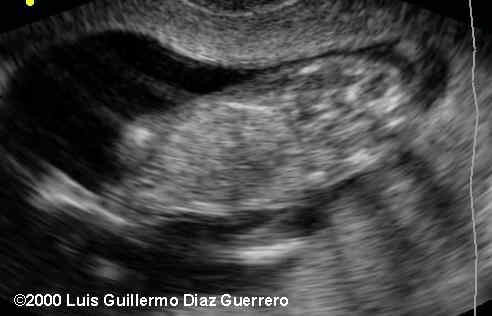

The back of the head

In order for the head to be in such an unusual position, the spine has to be very abnormal, and this was the very difficult part of this case: at 12 weeks the spine is barely visible. If this had been an older fetus, findings a crooked spine with a retroflexed head would have suggested Iniencephaly, which is what this case represented.

The pregnancy was interrupted. The pathology specimen shows a perfect correlation with the echographic findings. Notice the spine in the second image. This is very typical of ininencephaly.

• Marked hyperextension of the fetal head, very short, lordotic, cervical spine.

• Perpendicular face in relation with body axis

• Occiput absence without nuchal depression

• Open cervical spine with meningocele